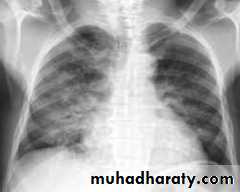

Lobar pneumonia: homogenous consolidation of one or more lung lobes, often with associated pleural effusion

A chest X-ray is usually sufficient to confirm the clinical diagnosis of pneumonia.

In lobar pneumonia, a homogenous opacity localized to the affected lobe or segment usually appears within 12 – 18 hours of the onset of illness.

Chest X-ray helps in:• Differentiating CAP from other diagnosis

• Provide information about severity (cavitation and multilobar involvement)

• Detects complications (pleural effusion or abscess formation).

• It can occasionally suggest an aetiological agent (pneumatocoele in Staphylococcus aureus pneumonia).